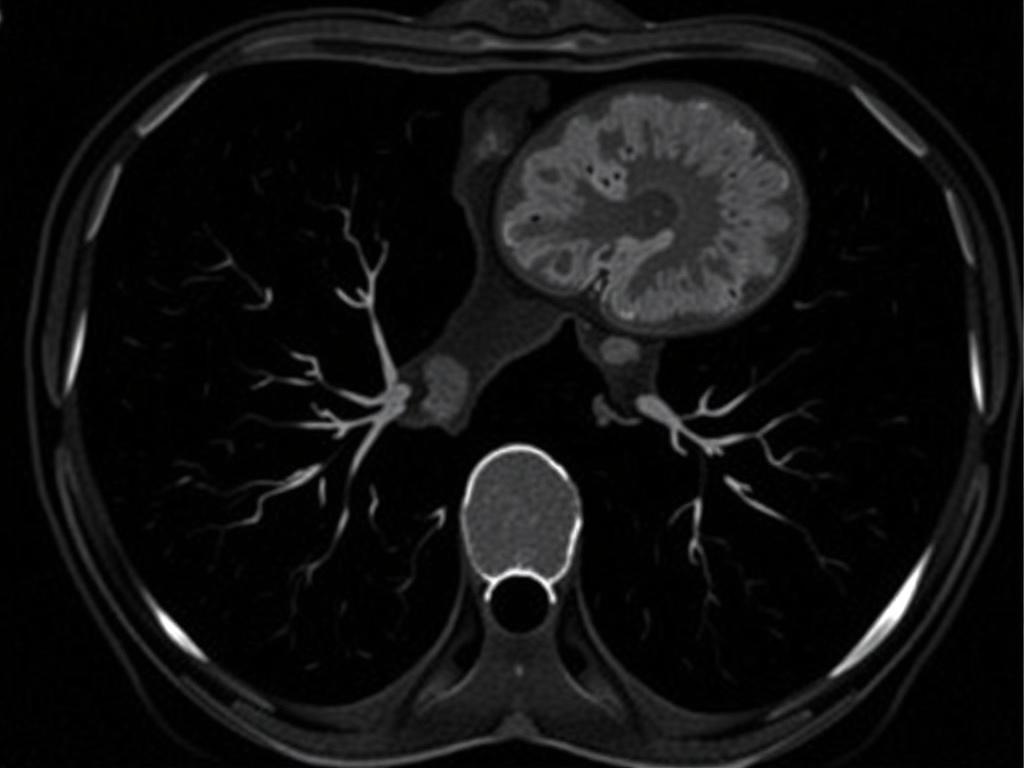

Интерпретация основана на том, как образование ведет себя в разных фазах. Ключевые признаки — плотность в нативной фазе, характер усиления в артериальной фазе и поведение в портальной фазе. Понимание закономерностей позволяет отличить, например, гемангиому от метастаза.

Ниже приводится краткая таблица типичных характеристик для часто встречающихся находок. Это обобщение, и всегда нужна клиническая корреляция с другими данными.

| Патология | Нативная фаза (HU) | Поведение при контрасте | Ключевая подсказка |

|---|---|---|---|

| Простая киста | ~0–20 HU | Без усиления | Чёткие края, жидкостная плотность |

| Гемангиома | ~20–40 HU | Периферическое узловатое усиление с центробежным заполнением | В позд. фазах часто равномерное накопление |

| Фокальная узловая гиперплазия (FNH) | ~40–60 HU | Гомогенное гипернасыщение в артериальной фазе, без явного вымывания | Центральный рубец у части случаев |

| Гепатоцеллюлярная карцинома (ГЦК) | Переменная | Артериальная гиперваскулярность и последующее вымывание в портальной/поздней фазах | Артериальное усиление с «wash-out» |

| Метастаз | Переменная | Часто гипо- или гипоусиление в портальной фазе; характер зависит от первичного очага | Множественные очаги, разная форма |

Важно помнить, что одно изображение редко дает однозначный ответ. Часто требуется сравнение с предыдущими снимками, анализ крови и, при необходимости, дополнительные методы, например МРТ с контрастом для уточнения диагноза.